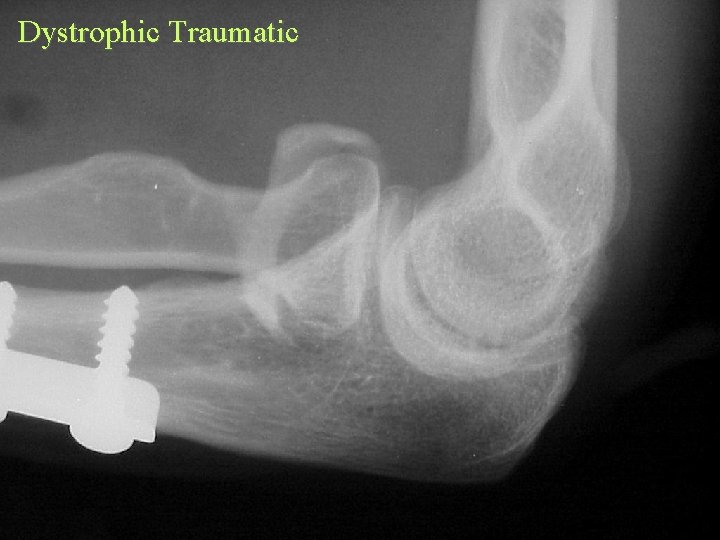

Ossification Traumatic Burns • Commonly elbow • Occurs distal to burn

Burn

Dystrophic Traumatic